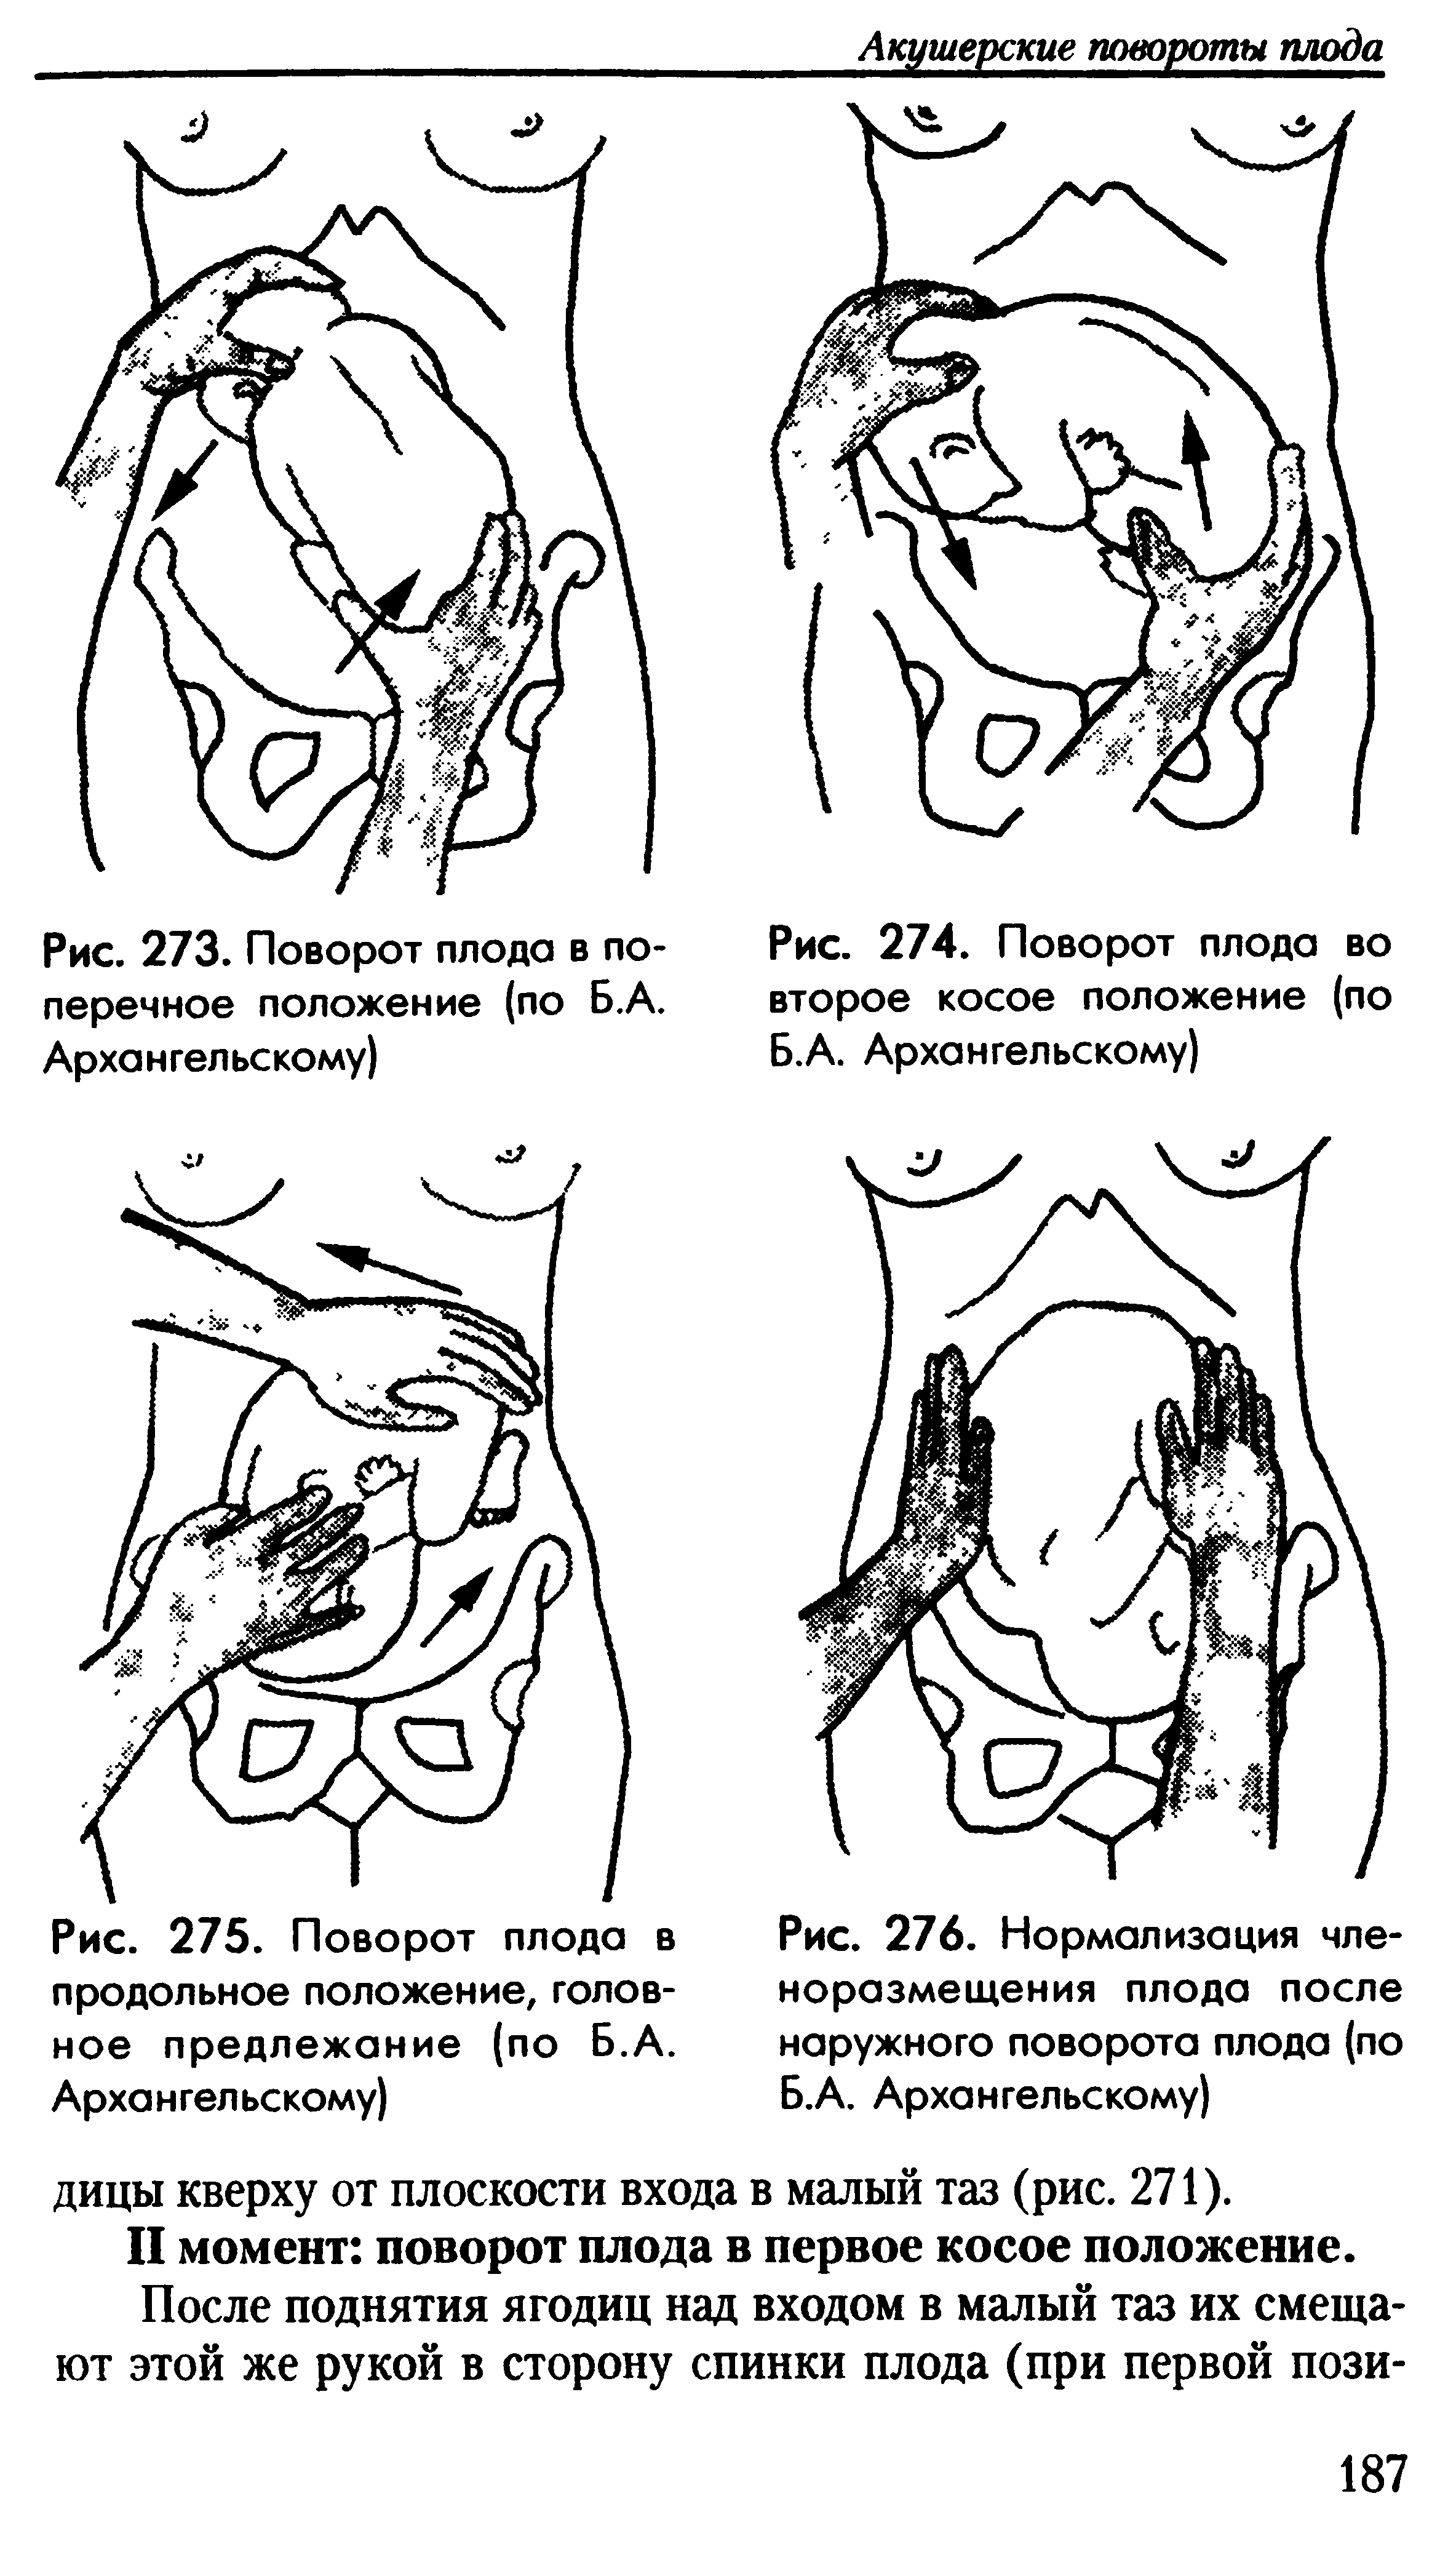

External Cephalic Version(ECV) technique for Breech Baby

Фото положения плода во время беременности

Ниже приведены несколько фотографий, которые помогут вам визуализировать положение плода во время беременности.